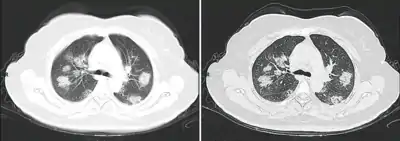

Dégâts pulmonaires

Les études en microscopie électronique et sur coupes histologiques de tissus pulmonaires (faites après autopsies) ont montré que les virions sont dans le poumon essentiellement localisés dans les pneumocytes[200].

Comme dans le cas du SARS, puis du MERS, la Covid se traduit dans l'arbre respiratoire par des lésions alvéolaires diffuses, caractérisées par des phases exsudatives et prolifératives de ces lésions, avec une congestion des vaisseaux capillaires et une nécrose systématique des pneumocytes, et très souvent une atteinte des membranes hyalines, un œdème interstitiel et intra-alvéolaire.